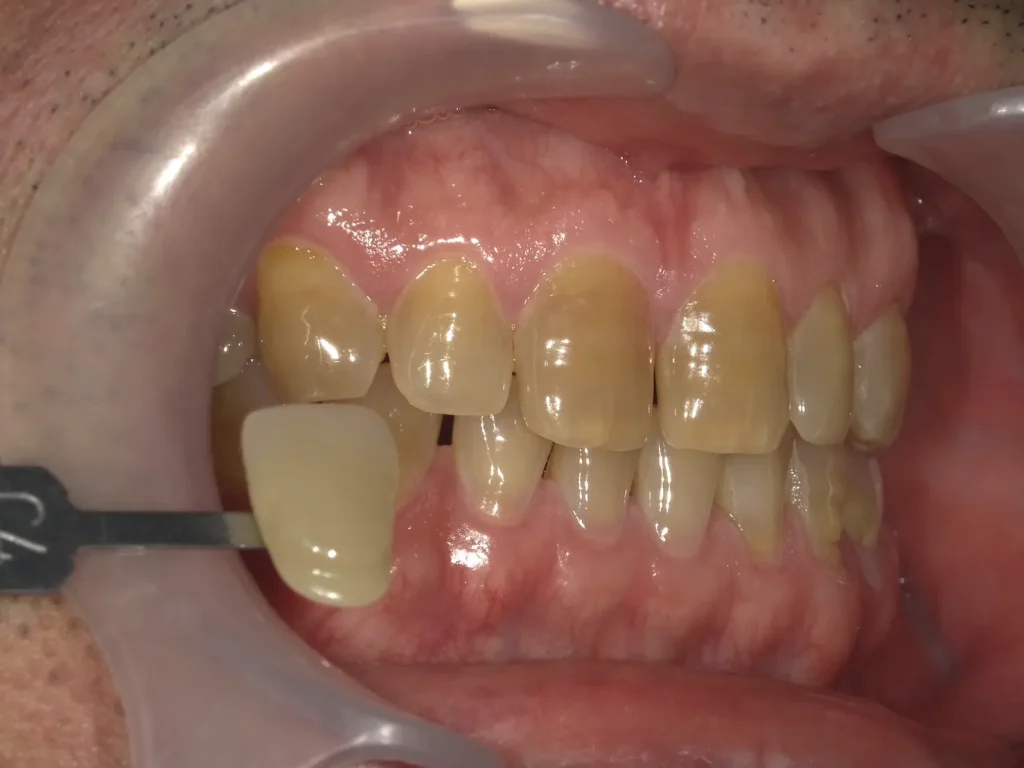

ホワイトニングサロンReflet福岡天神店の症例です。

50代男性

せめて人並みの歯の色にしたい。

もし白くできるなら、もう少し上を目ざしたい気持ちもあるのでがんばりたい。

ホワイトニング施術内容

初回プレミアムホワイトニング 7400円

デュアルホワイトニング(プレミアムコース)

110,000円

(プレミアムホワイトニング5回・ホームホワイトニング上下セット・ホームジェル12本・トリートメントペースト1本)

ホワイトニング期間

約2ヶ月半

術前術後写真